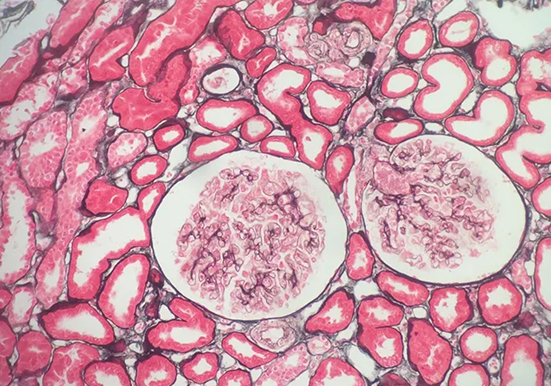

刚果红染色是一种常用的生物染色方法,以下是关于它的详细介绍:

染色原理:主要依赖于其与蛋白质及其他生物大分子的亲和性,通过静电吸引、氢键等作用力与样品中的不同组分发生相互作用,使样品呈现出特定的颜色。

染色:将切片放入刚果红工作液中染色 10min,然后用流水冲洗 1min。